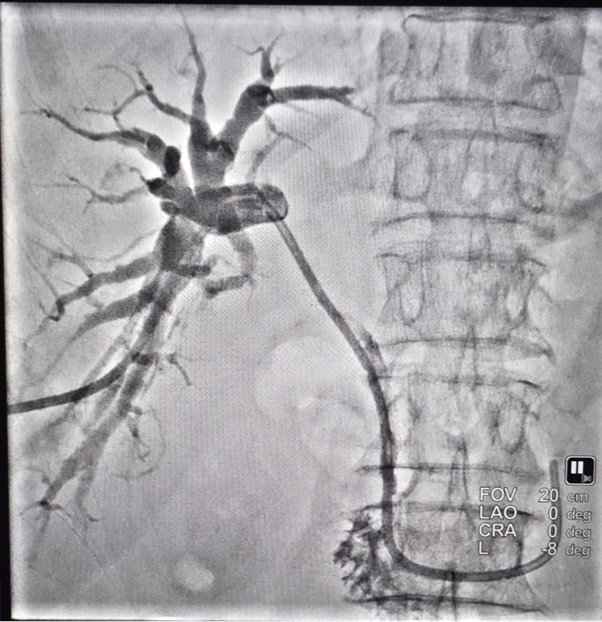

Percutaneous Transhepatic Biliary Drainage (PTBD) is a safe, minimally invasive procedure where:

• A thin tube is gently placed through the liver into the blocked bile duct.

• Sometimes, a stent (self-expandable metallic stent) keeps the duct open longer.